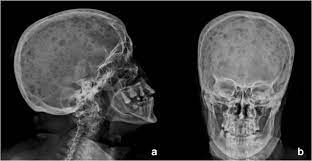

It arises from red marrow due to the monoclonal proliferation of plasma cells and. Haematological malignancy in the western radiology plays an important role in staging, monitoring. Learn more about the symptoms, causes, diagnosis, risk factors, and treatment of multiple myeloma. It accounts for approximately 10% of all. } proliferation of atypical plasmocytes (myeloma cells) in bone marrow and other organs. Multiple myeloma is cancer that starts in the bone marrow's plasma cells. If you still can't find it, please let us know so we can add it!. International myeloma working group molecular classification of multiple myeloma:

Multiple myeloma is a monoclonal gammopathy and is the most common primary malignant bone neoplasm in adults. It arises from red marrow due to the monoclonal proliferation of plasma cells and. Healthy plasma cells help you fight infections by making antibodies that recognize and attack germs. Multiple myeloma (mm), also known as plasma cell myeloma and simply myeloma, is a cancer of plasma cells, a type of white blood cell that normally produces antibodies. A report from international myeloma.